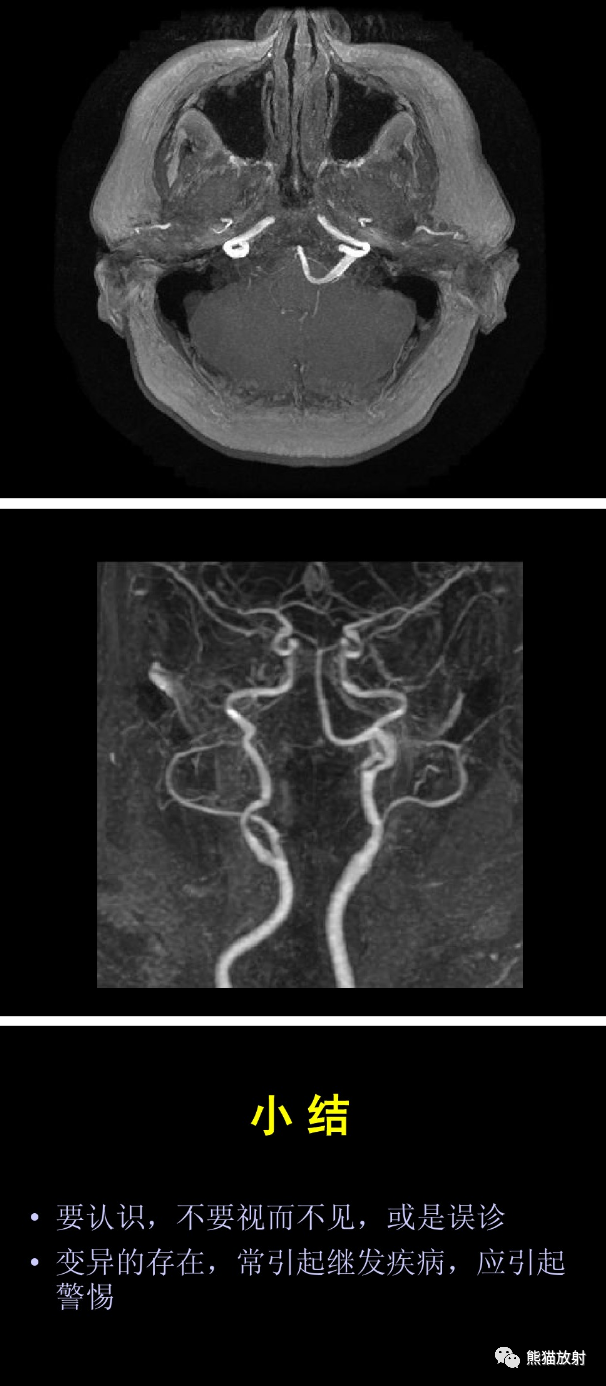

大脑前动脉 ACA,大脑中动脉 MCA,大脑后动脉 PCA,前交通动脉 ACoA,后交通动脉 PCoA,颈内动脉 ICA